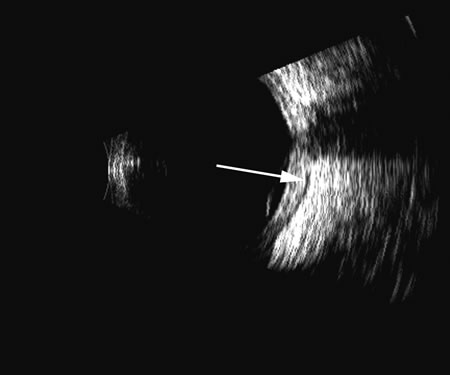

of these features of a PLM are demonstrated in Figure 7, whereas Figure 8 shows a typical detached retina. Hemorrhage shows good echogenic properties and presents a typical highly reflective vitreous body (Figs. 9 and 10). Asteroid hyalosis may resemble a vitreous hemorrhage except that the individual calcium deposits are even more reflective than hemorrhage and usually there is a clear anechoic zone between the retina and the retracted primary vitreous (Fig. 11). Synchysis scintillans is another condition with highly reflective regions in the vitreous due to cholesterol crystals. It is identifiable by the kinetic scan pattern of floating “snowflakes” that settle when the eye stops moving, just like the snowflakes in a child's snow globe. Since the “normal” vitreous is usually dissolved in this condition, the echoes come to rest on the retinal surface when the eye stops moving. An area or region of attachment of presumed vitreous to the ocular wall can be seen with kinetic scans and may indicate an area of stress or possible retinal tear. In diabetic retinopathy with proliferative membranes, the vitreous is often attached to a membrane, producing a typical cross-shaped elevation on a scan through the long axis of the proliferans. Right-angle or three-dimensional scans show the folded nature of the retinitis proliferans membrane (see Fig. 13). |